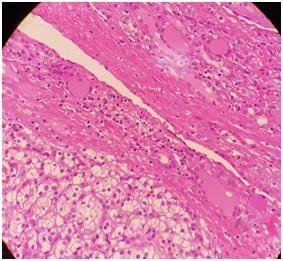

In May 2016, CT thorax abdomen and pelvis for assessment of weight loss revealed no evidence of renal cancer recurrence, but there was a heterogenous right thyroid lobe lesion measuring 2.3cmx1.8cm. Subsequent ultrasound assessment of this thyroid lesion showed a right lobe solid and isoechoic nodule with few cystic areas measuring 3.5x2.74cm. There were other small nodules less than 0.5cm in the left lobe. Fine needle aspiration (FNA) and cytology of the right lobe nodule in June 2016 was suboptimal, repeat FNA and cytology around 2weeks later was of borderline adequacy and the findings were non-specific. He proceeded for total thyroidectomy in July 2016, the histology revealed clear cell neoplasm with morphic features in keeping with metastatic renal cell carcinoma (Figure 1&2). Immuno- histochemical stain showed that the tumor was negative for thyroid transcription factor -1 (TTF-1) (Figure 3) and positive for CD10 (Figure 4). He was commenced on thyroid hormone replacement following thyroidectomy. Postoperative staging with positron emission tomography (PET) scan was unremarkable.6

Figure 1&2 Show the interface between normal thyroid tissue and the tumor.